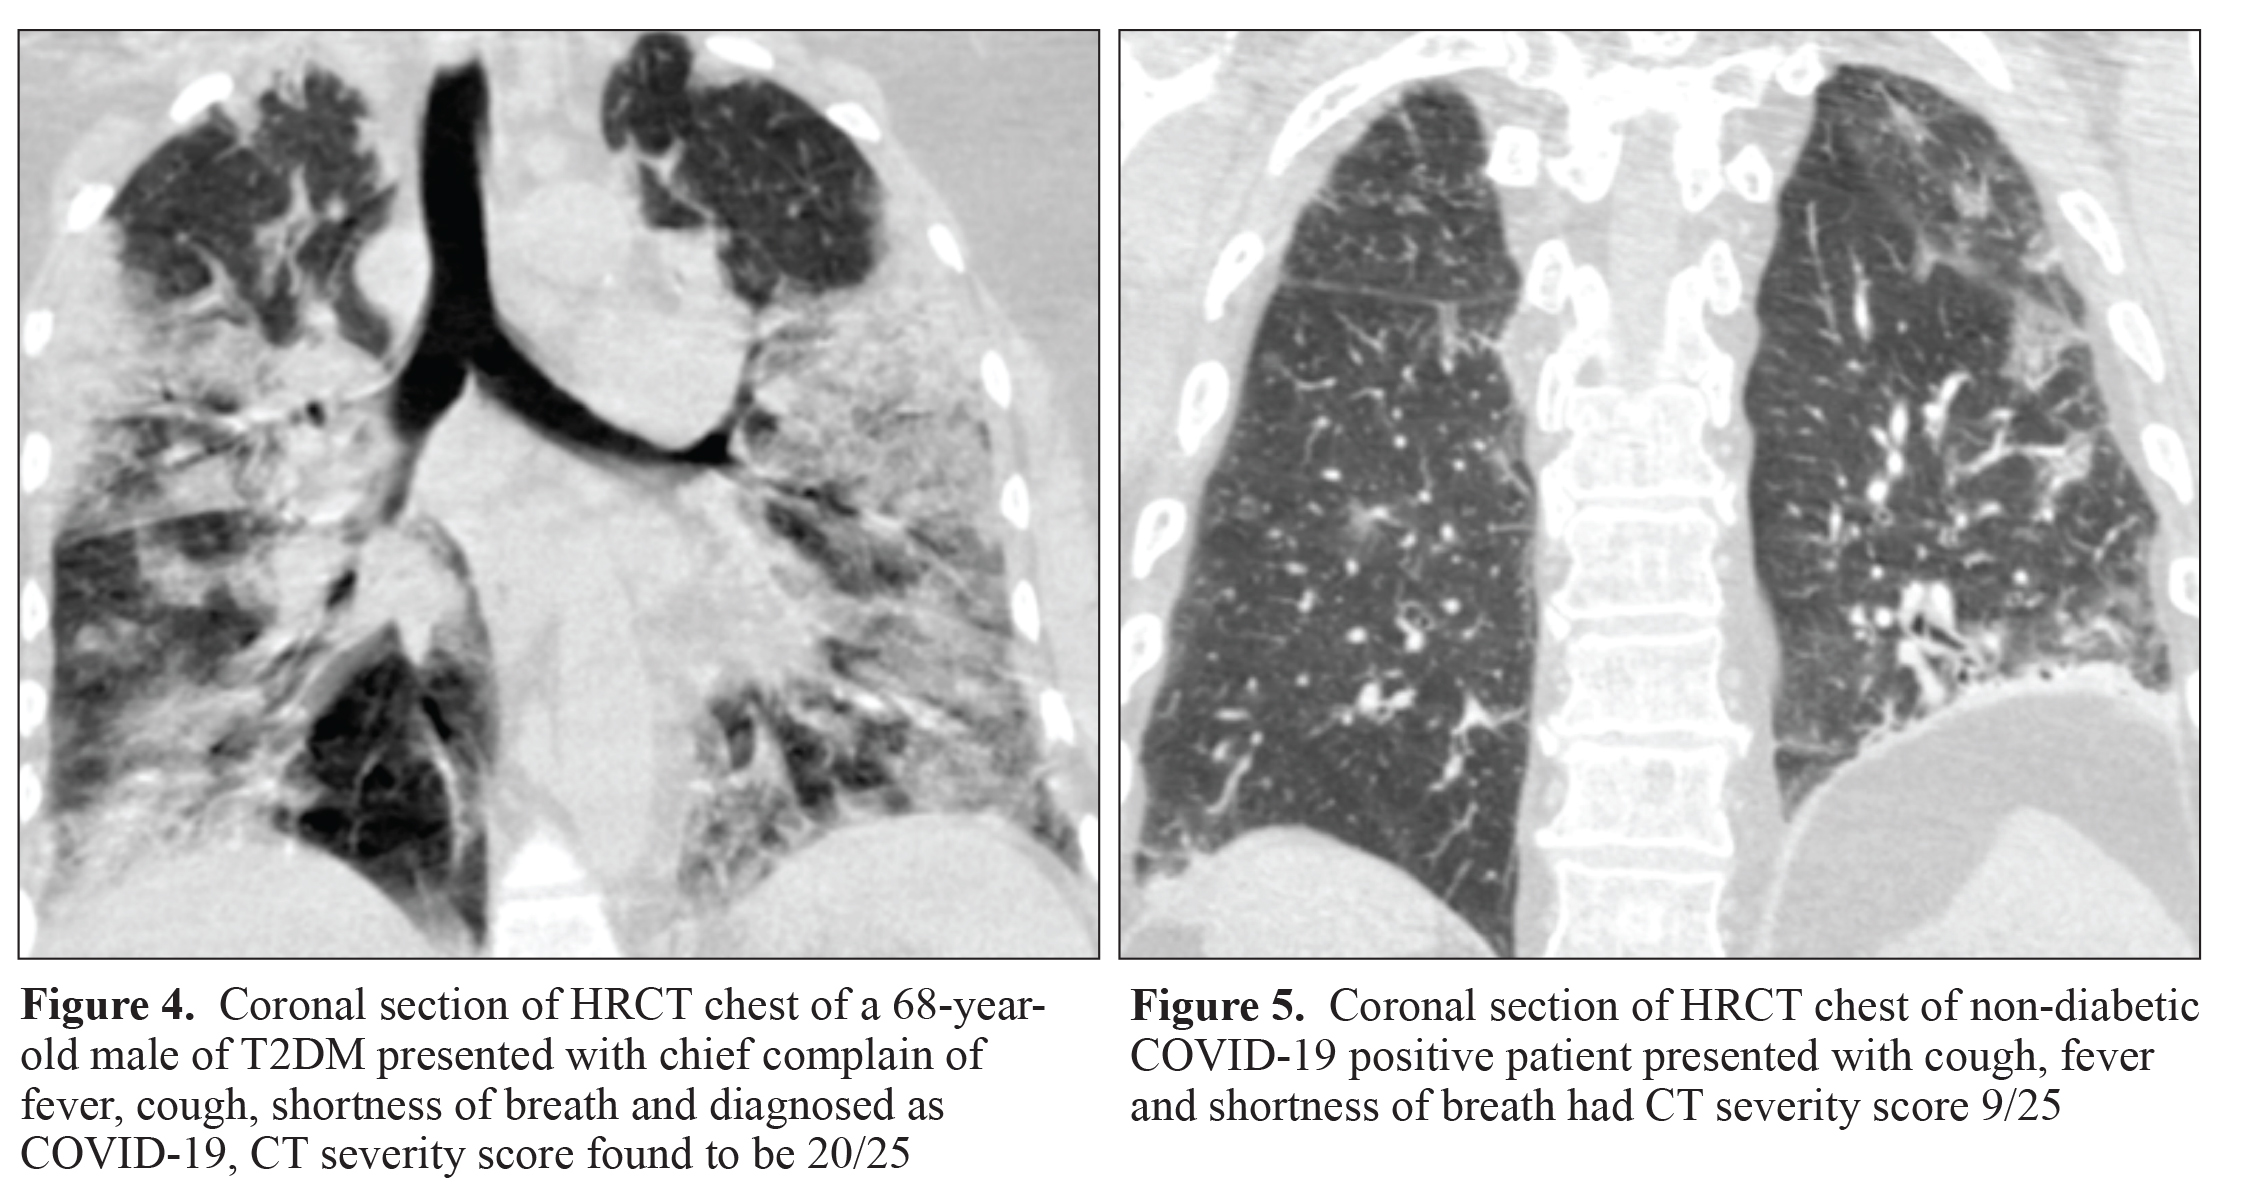

Digital chest radiograph (CXR) of all patients, USG chest of 248 patients (14.76%) and HRCT chest of 512 patients (30.48%)were available for analysis. In the study population, CXR represented a classic picture for COVID images in 244 patients(14.52%) with an average visual score of 0.69 (95% CI: 0.69±0.45, SD=0.83) out of 4. USG severity score was 14.96 (95%CI: 14.96±4.62, SD=8.92) out of 14 and an average CT severity score of 6.04 (95% CI: 6.04±1.33, SD=5.75) out of 25. TheCT severity scores were >10/25 in 100 patients (19.53%). Results of radiological findings in diabetes and non-diabetes groupwere as follows: CXR average visual score was 0.88 and 0.61 (p<0.001) while classic for COVID images in 21.82% and11.94% patients (p<0.001) among Group 1 and 2 respectively. The CT severity score was significantly high in the diabetesgroup (7.25) as compared to the non-diabetes group (5.67) (p=0.0054) (Figure 2 and 3). The CT severity score was >10/25in 30.56% and 15.22% patients in respective groups (p<0.001)

Digital chest radiograph (CXR) of all patients, USG chest of 200 patients (15.87%) and HRCT chest of 424 patients (33.65%)was available for analysis. CXR depicted a classic for COVID images in 208 patients (16.51%) with an average visual score of0.63±0.81 out of 4. USG severity score was 14.88±9.18 out of 14 and average CT severity score was observed to be 5.81±5.44out of 25 with CT severity score >10/25 in 80 patients (18.87%) (Figure 4 and 5). Radiological findings observed amongdiabetes group and non-diabetes group without comorbidities were as follow: The CXR average visual score was 0.74 and 0.58(p=0.0035) while classic for COVID images was observed in 28.57% and 13.06% patients (p<0.001) in Group 3 and Group4 respectively. USG chest severity score was significantly higher in diabetes group (17.86) as compared to the non-diabetesgroup (13.48) (p=0.0041) (Figure 6 and 7). CT severity score was 7.24 in the diabetes group and 5.32 in the non-diabetesgroup (p=0.0020) with a CT severity score >10/25 in 29.41% and 15.53% patients in the respective groups (p=0.0018).

Radiological imaging of chest provides an important clue regarding lung involvement in COVID-19 that is a prognosticindicator of disease severity. Digital chest X-ray imaging suggested a higher proportion of sample population exhibiting lung involvement in diabetics as compared to that observed in non-diabetics. A similar picture was portrayed by CT severityscore that was high in diabetic patients as compared to the findings of non-diabetics. However, USG chest severity score wassignificantly increased in the isolated diabetic group as compared to the non-diabetes group without other comorbidities. Theaforementioned findings suggest a severe form of pneumonia in diabetic patients as compared to the non-diabetic patients.Moreover, COVID-19 manifestation and its severity are adversely affected by the associated comorbid disease. In the presentstudy, clinical presentation and laboratory parameters indicated a significant difference among isolated diabetes and the non-diabetes group without comorbidities, compared to groups, with comorbidities.